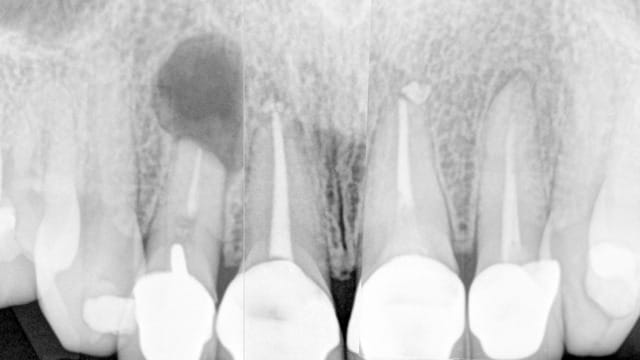

Cette patiente de 27 ans, vient me consulter après que son dentiste l'ai envoyé chez un stomato pour une résection apicale.

Elle a un sourire gingival.

-Quel est le résultat de cette résection, pour l'instant avec juste cette radio, c'est pas fameux?

15 jours avant les radios.

comment ça pourrait marcher sans retraiter les racines?

au jour de la consult aucun.

non juste caries, 4-5 ans.